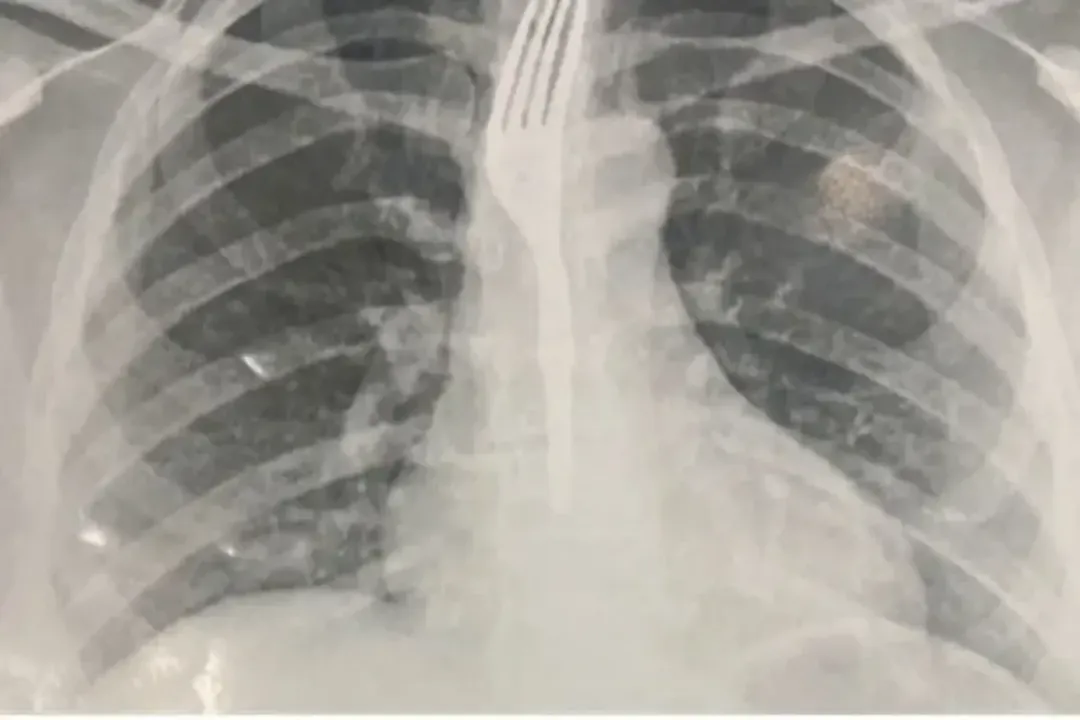

Conforme o site Achei Sudoeste, ela foi levada ao Hospital Geral de Guanambi (HGG), onde exames de imagem mostraram que o utensílio estava preso no esôfago, em posição de risco.